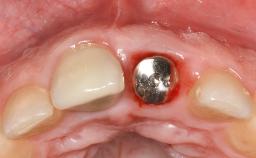

Reconstructive Treatment of a Peri-Implantitis Defect at an Implant in a Mandibular Molar Site

In this case, Mario Roccuzzo utilizes surgical bone regeneration treatment around implant 46 using a bone graft substitute and a connective tissue graft to resolve peri-implant inflammation, reduce the probing depths, and prevent further progression of disease.